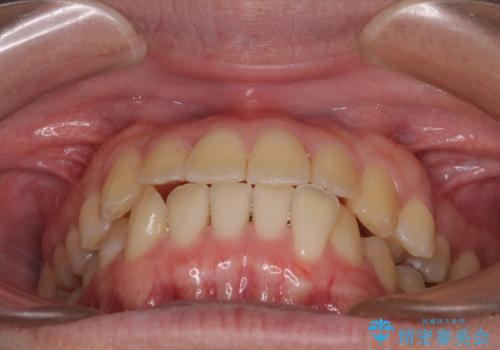

【モニター】前歯のクロスバイトと隙間を改善 インビザラインによる矯正治療

- 前歯のクロスバイトを気にして来院された患者様です。

骨格的には問題がなかったため、インビザラインを用いて咬み合わせを改善していくこととしました。

インビザライン特有の、奥歯の咬み合わせの問題もなく、しっかりと歯列を改善することができました。

舌側転位している上顎側切歯(内側に引っ込んでいる真ん中から2番目の歯)は、インビザラインが最も移動を苦手とする歯であり、これ以上の改善を望まれる場合にはワイヤー矯正、あるいはワイヤー矯正の併用をお勧めいたします。